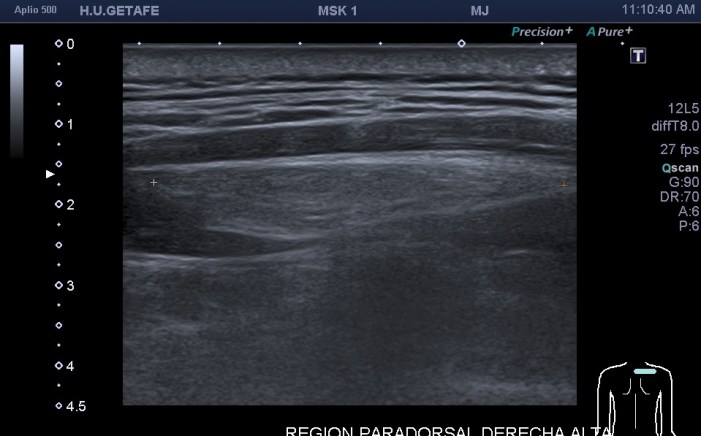

Como hoy quiero que este post sea muy visual y de poca lectura te voy a mostrar los diferentes lugares claves y básicos para que puedas estar atenta en las exploraciones para buscar líquido en estas localizaciones. Primera imagen de normalidad, segunda imagen de «no normalidad» y anatomía y ordenada según la clasificación que has visto un poco más arriba.